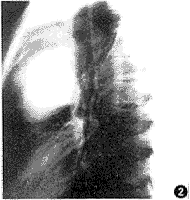

X线检查: 正位胸片示左侧胸腔一12.0cm×7.0cm长椭圆形块影,边缘光滑,密度均匀,基底部与纵隔左缘相连;侧位见块影居纵隔前上方,略呈分叶状,其上缘见条状钙化影(图1、2)。